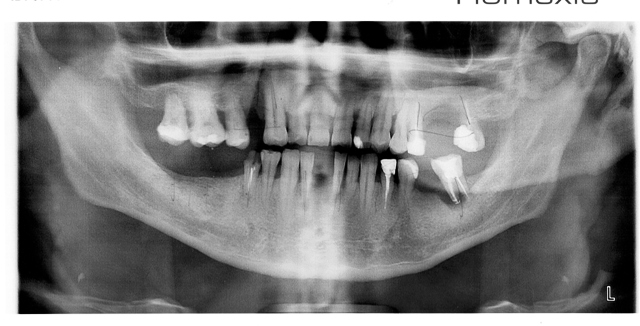

Гадание на ренгеновском снимке [Re: Doctor]

1 октября 2013 в 20:34 Гілками Прикріплені файли (0 завантажити)

Вобщем,почти что решились на манипуляции с зубами, тем более, что ситуация поджимает - от парадонтоза потеряли ещё один зуб. Наконец то сделали развётнутый 3Д снимок зубов за 185 грн., кто что может из специалистов сказать по поводу данного снимка?

Какие манипуляции проводить? обрабатывать "Вектором", шинировать, ставить мосты, импланты?

Чего делать и по чём?

Заранее спасибо за квалифицированные ответы

Вобщем,почти что решились на манипуляции с зубами, тем более, что ситуация поджимает - от парадонтоза потеряли ещё один зуб. Наконец то сделали развётнутый 3Д снимок зубов за 185 грн